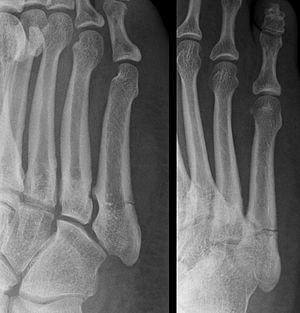

Proximal fractures of the fifth metatarsal bone:

- Proximal diaphysis, typically stress fracture.[12][13]

- Metaphysis: Jones fracture[14]

-Tuberosity: Pseudo-Jones fracture[15] (avulsion fracture).[15]

Other proximal fifth metatarsal fractures exist, although they are not as severe as a Jones fracture. If the fracture enters the intermetatarsal joint, it is a Jones fracture. If, however, it enters the tarsometatarsal joint, then it is an avulsion fracture caused by pull from the peroneus brevis. An avulsion fracture is sometimes called a Pseudo-Jones fracture or a Dancer's fracture.

This injury should be differentiated from the developmental "apophysis" which is the secondary ossification center of the metatarsal bone. It is normally occurring at this site in adolescents. Differentiation is possible by characteristics such as absence of sclerosis of the fractured edges (in acute cases) and orientation of the lucent line: transverse (at 90 degrees) to the metatarsal axis for the fracture (due to avulsion pull by the peroneus brevis muscle inserting at the proximal tip) – and parallel to the metatarsal axis in the case of the apophysis.

For several reasons, a Jones fracture may not unite. The diaphyseal bone (zone II), where the fracture occurs, is an area of potentially poor blood supply, existing in a watershed area between two blood supplies. This may compromise healing. In addition, there are various tendons, including the peroneus brevis and fibularis tertius, and two small muscles attached to the bone. These may pull the fracture apart and prevent healing.

Zones I and III have been associated with relatively guaranteed union and this union has taken place with only limited restriction of activity combined with early immobilization. On the other hand, zone II has been associated with either delayed or non-union and, consequently, it has been generally agreed that fractures in this area should be considered for some form of internal immobilization, such as internal screw fixation.

These zones can be identified anatomically and on x-ray adding to the clinical usefulness of this classification.[18] Surgical intervention is not, by itself, a guarantee of cure and has its own complication rate. Other reviews of the literature have concluded that conservative, non-operative, treatment is an acceptable option for the non-athlete.[19]